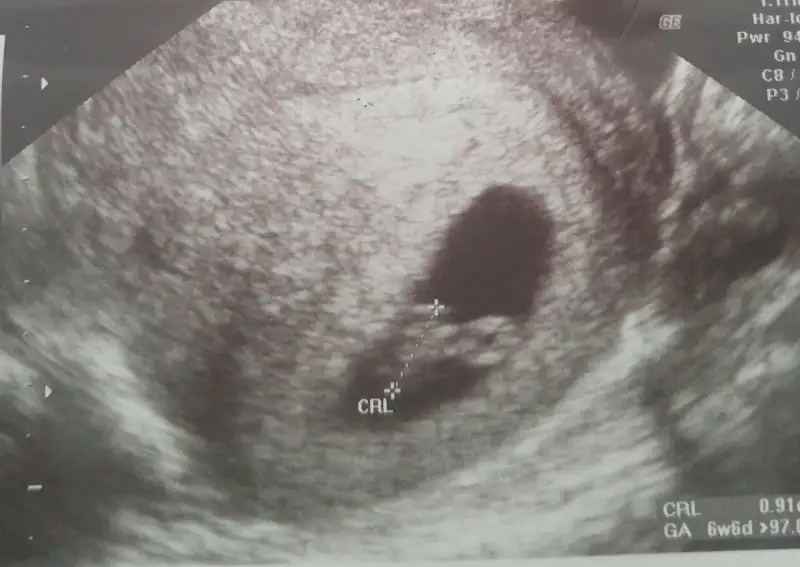

Hazirandaki gebeliğim sonlandı maalesef.pıhtılaşma olmuş ve bebeğimin kalbi durmuş.şimdi allahın izniyle tekrar hamileyim kan suşandırıcı iğne kullanıyyorum.yorum yaparmısınız usg lere.2 side karından .ilk resim 7 hafta 2.si 6+3.

Canim karindan ultrasyon sanirim burdaki teoriye gore kiz. Ama burdaki teori venimkinde tutmadi bende 6 haziranda dogum yaptim ve bebegim oglandi. Seninki benimkine cok benziyor

Allah bağışlasın canım.evet karından,bir kızım var 7 yaşında buda 2. Miz :) kızıma kızkardeş mi erkek kardeş mi gelecek bakalım.12.haftada gideceğim tekrar belkş Dr bi tahmin yapar